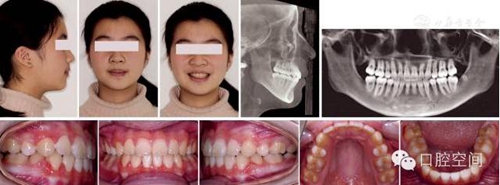

女性,11歲,表現(xiàn)為骨型Ⅱ類錯(cuò)頜畸形,高角,下頜后縮,上下牙弓前突。X線片顯示正處于生長發(fā)育高峰期。治療前面頜像及X線片見圖2。通過拔除4個(gè)第一前磨牙,應(yīng)用標(biāo)準(zhǔn)方絲弓定向力技術(shù)矯治,并在上頜第一磨牙近中植入種植體。初始弓絲上頜為0.017×0.022英寸不銹鋼方絲(1英寸=2.54 cm),下頜為0.018×0.025英寸不銹鋼方絲,佩戴高位J鉤牽引頭帽12小時(shí)/天,先牽引尖牙往遠(yuǎn)中,再換用0.020×0.028英寸和0.019×0.025英寸不銹鋼方絲分別彎制關(guān)閉曲內(nèi)收上下切牙關(guān)閉間隙,在內(nèi)收前牙的同時(shí),對上頜后牙進(jìn)行垂直向的主動(dòng)壓低。間隙關(guān)閉后應(yīng)用10-2支抗預(yù)備系統(tǒng)直立下頜后牙,上頜始終通過高位J鉤牽引頭帽進(jìn)行垂直向控制。最后下頜換用0.0215×0.028英寸全尺寸弓絲穩(wěn)定下牙列,使用Ⅱ類牽引和垂直牽引,對Ⅱ類關(guān)系進(jìn)行過矯正。治療中面頜像見圖3。通過25個(gè)月的矯治,拆除矯治器,制作佩戴保持器。治療后FMA減少了1°,F(xiàn)MIA和Z角均接近正常值(表3),下頜骨垂直向生長明顯,治療后面型明顯改善,咬合關(guān)系良好。治療后面頜像及X線片見圖4,治療前后頭影測量對比圖見圖5。

圖2典型病例治療前面像及X線片

圖4典型病例治療后面像及X線片